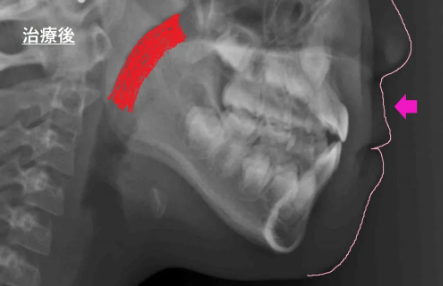

このレントゲンは、頭部X線規格写真(セファログラム)というもので、矯正治療を行う際に特に多く撮影されるものです。

要は、お顔全体の横顔の骨格をみています。

- 歯の咬み方が正常になりつつあります。(上の歯が、下の歯を覆いかぶさるのが正常です)

- 横顔の、上あごの部分が出てきています!!(矢印の部分です)

要は、上顎が成長してきています! - 気道が広くなっています!!!!(治療前はオレンジの部分、治療後は赤い部分。赤い部分が広くなっているのがわかりますか?ここが気道で、広いほうが呼吸がしやすいです!!!!)

実際、Pちゃんもマウスピース入れていても、息がしやすくなった!と効果を実感していました!!とこんなふうに、マウスピースをがんばると、様々な副産物があるんです☆☆☆